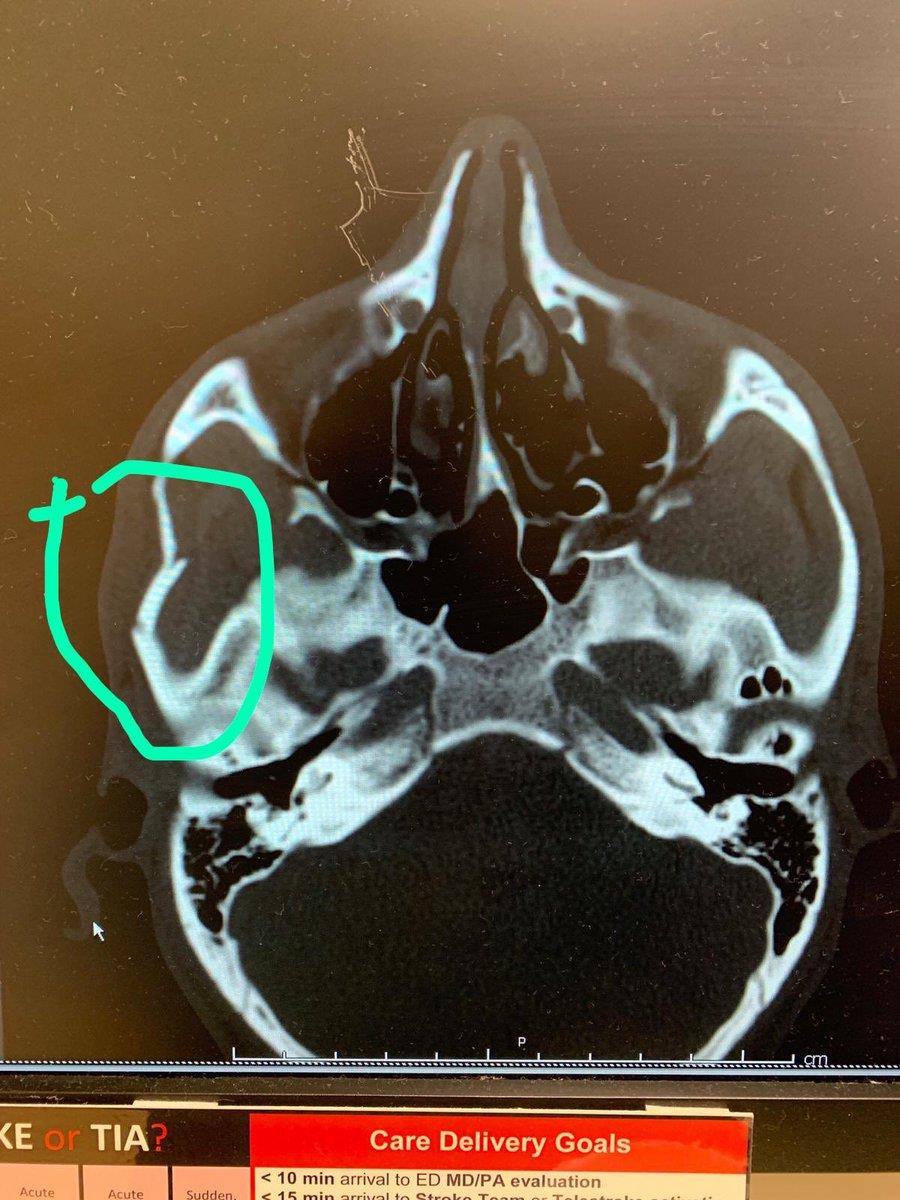

Ливийский оборонец футбольного клуба Лос-Анджелес Мохаммед Эль-Мунир ляжет под нож хирурга, сообщает журналист Амро Тарек.

В одном из эпизодов матча Лос-Анджелеса против соседей из Гэлакси Ибрагимович ударил локтем Эль-Мунира.

Это привело к серьезной травме черепа защитника.